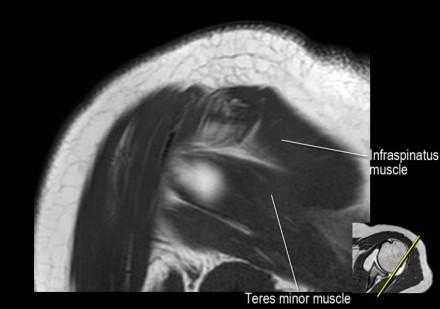

Изображение задних отделов плечевого сустава.

Отображены надостная, подостная и малая круглая мышцы и их сухожилия. Все они прикрепляются к большому бугорку плечевой кости. Сухожилия и мышцы манжеты вращателей участвуют в стабилизации плечевого сустава во время движения. Без манжеты вращателей головка плечевой кости частично сместилась бы из суставной впадины, уменьшив силу отведения дельтовидной мышцы (мышцы вращательной манжеты координирует усилия дельтовидной мышцы). Повреждение манжеты вращателей может привести к смещению головки плечевой кости кверху, в результате вызвая высокое стояние головки плечевой кости.